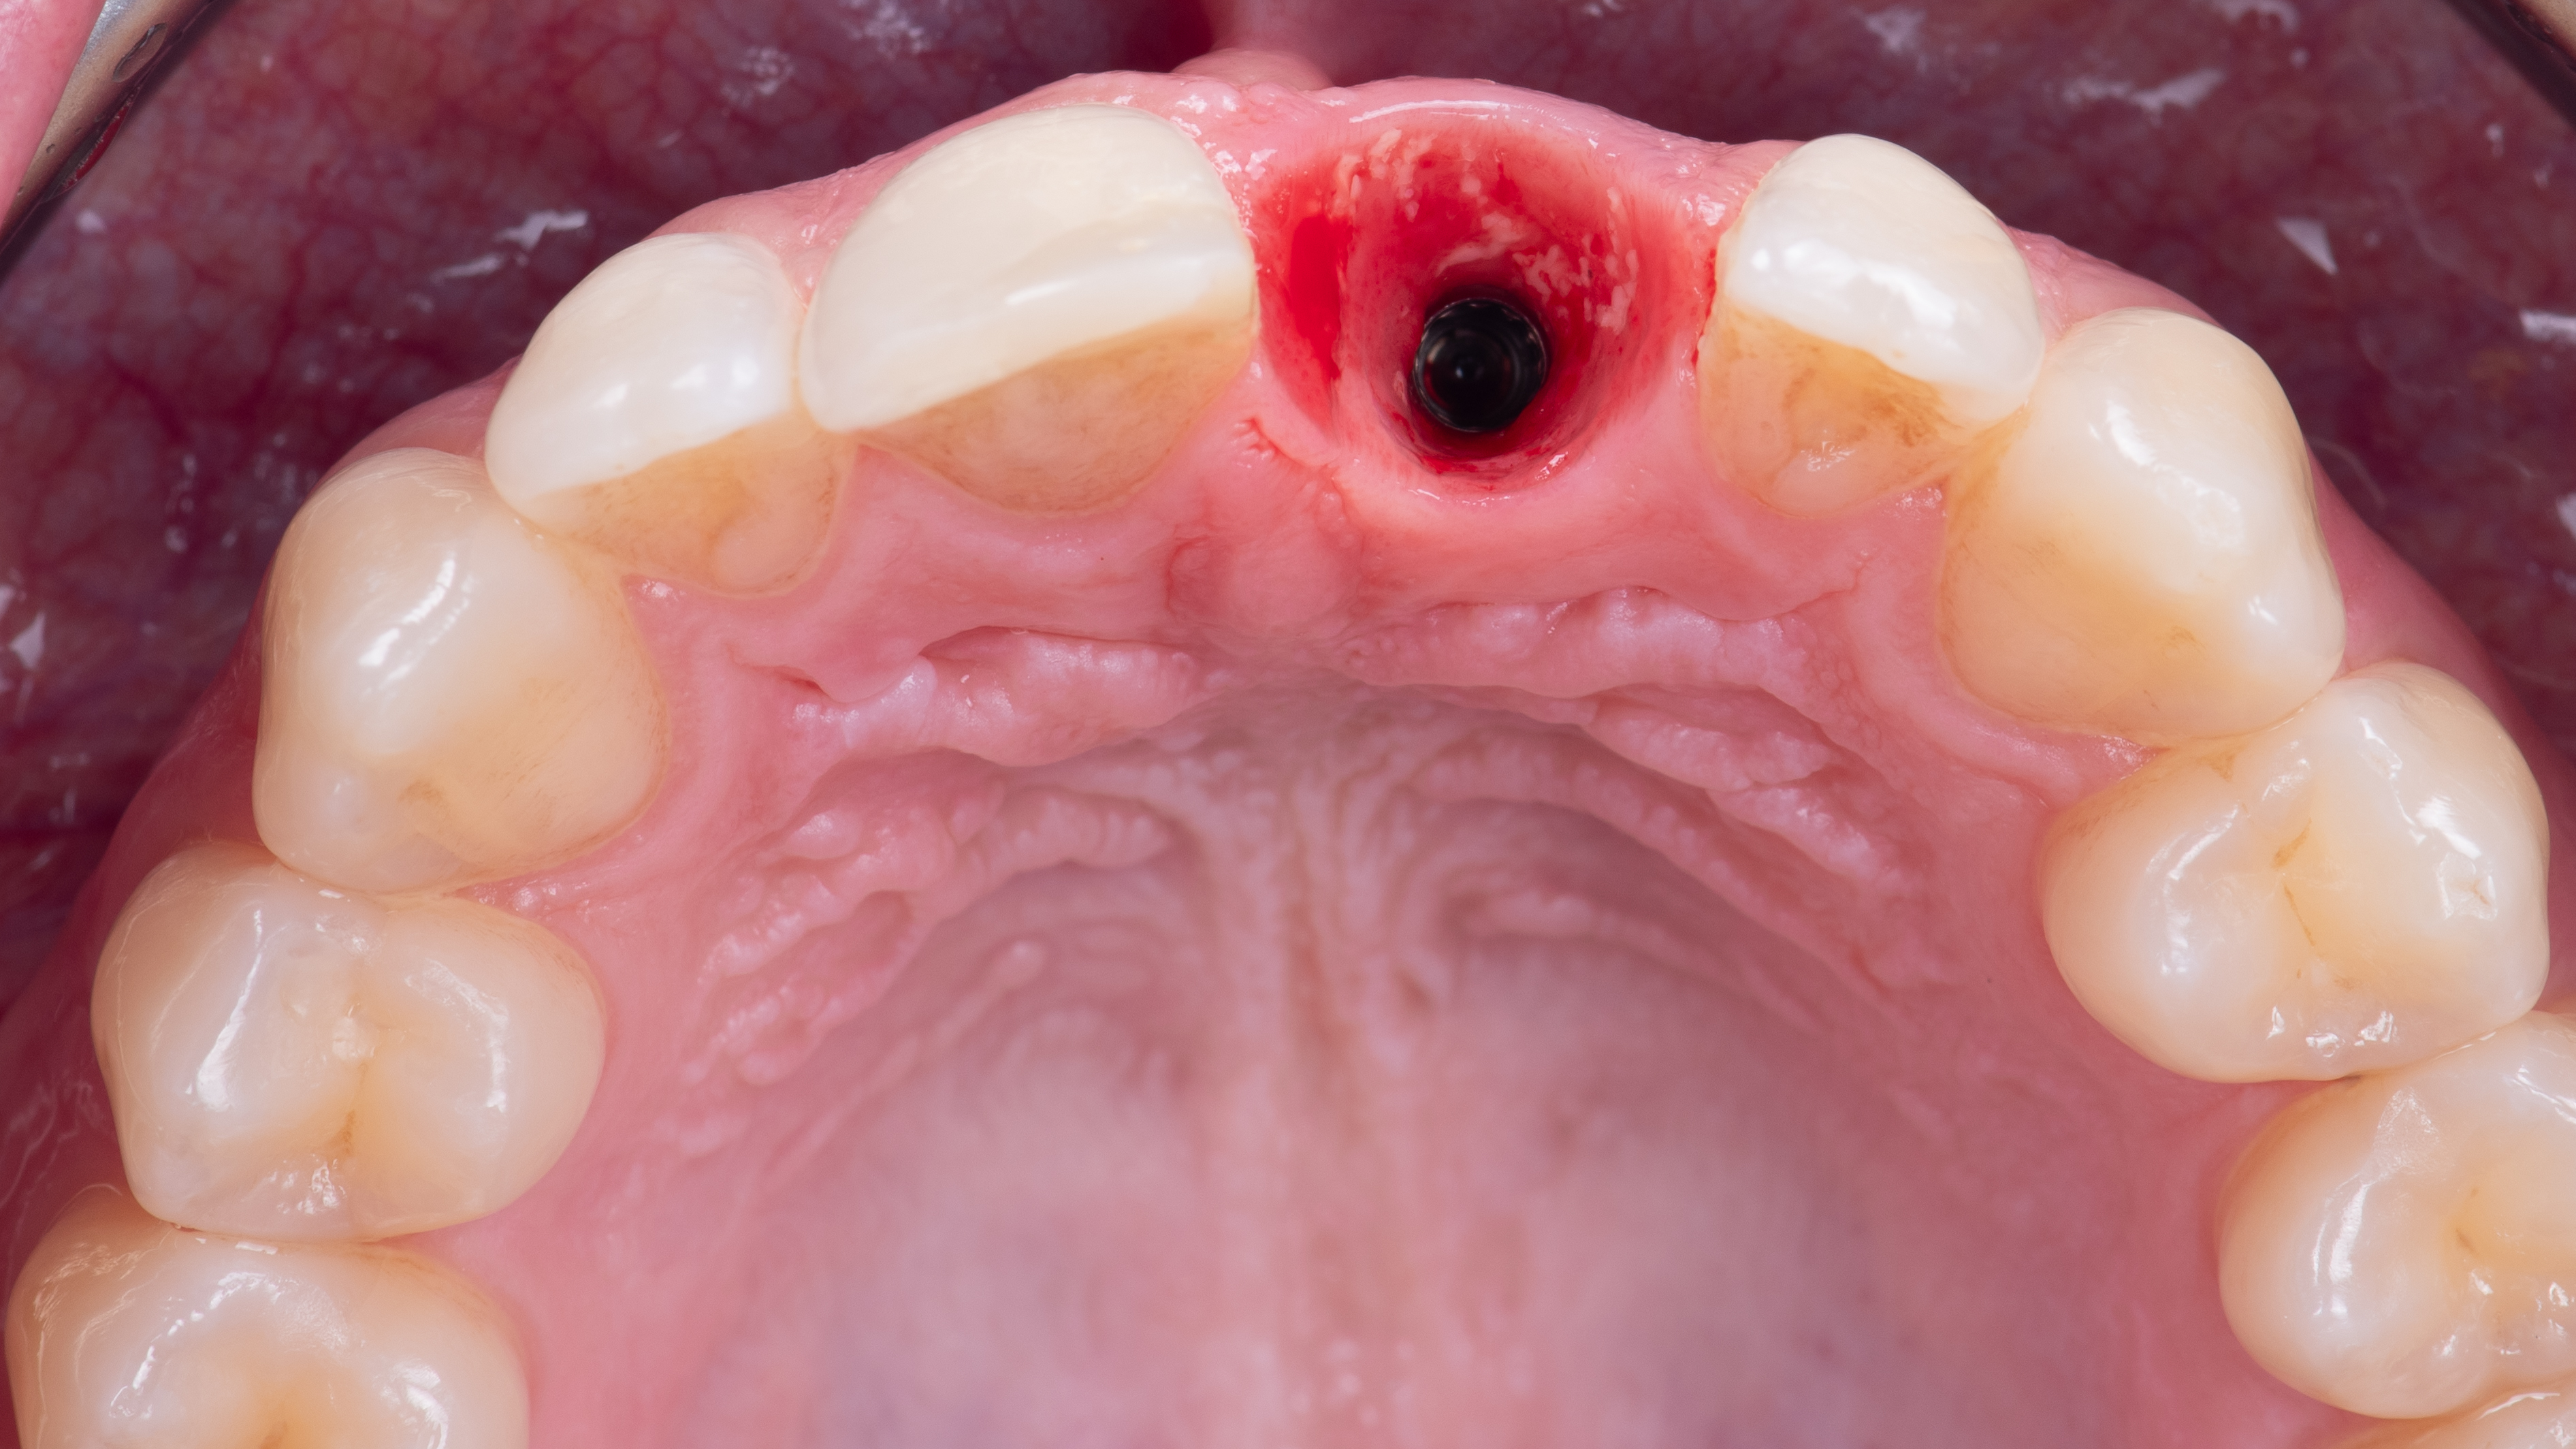

Extraction de la dent la plus atraumatique possible (Photo 10).